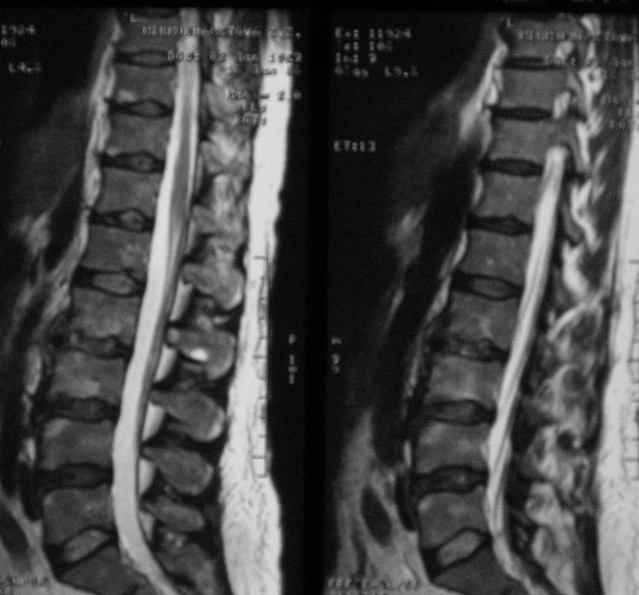

Отправляю MRI в динамике, снятые с пленки на фотоаппарат.

|

MRI через три недели

По данным представленных КТ и МРТ у больной имеется достаточно выраженная степень деструкции тел позвонков (около 30% общей костной массы тела позвонка), что определяет высокий риск возникновения патогических переломов и появления локальной кифотической деформации на этом уровне.

Уважаемый доктор! судя по последнему МРТ процесс затрагивает соседние позвонки с переходом процесса через диск. Для туберкулёза как раз и характерна картинка "целующихся" позвонков. При бактериальном процессе диск страдает лишь вторично. Туберкулиновые пробы могут быть в пределах нормы, лёгкие - чистые. Вообще туберкулёз последнее время стал очень коварен и атипичен. Такие случаи отмечались у детей старшего возраста.